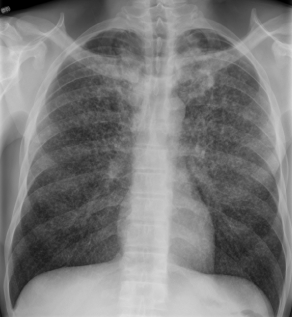

A 40-year-old man comes to the office due to progressively worsening shortness of breath and nonproductive cough over the last 3 weeks.  He also notes 2 months of fatigue, intermittent fever, and decreased appetite.  He has lost 6 kg (13.2 lb) during this period.  He has no other medical problems.  He has a history of intravenous drug use and a 20-pack-year smoking history.  The patient was released from a 2 year incarceration 6 months ago.  Temperature is 38.3 C (100.9 F) , blood pressure is 110/70 mm Hg, pulse is 90/min, and respirations are 18/min.  The patient is in no distress but has mild temporal wasting.  Crackles are present throughout the lung fields.  Heart sounds are normal.  There is mild hepatomegaly.  Chest x-ray is shown below. A 40-year-old man comes to the office due to progressively worsening shortness of breath and nonproductive cough over the last 3 weeks.  He also notes 2 months of fatigue, intermittent fever, and decreased appetite.  He has lost 6 kg (13.2 lb)  during this period.  He has no other medical problems.  He has a history of intravenous drug use and a 20-pack-year smoking history.  The patient was released from a 2 year incarceration 6 months ago.  Temperature is 38.3 C (100.9 F) , blood pressure is 110/70 mm Hg, pulse is 90/min, and respirations are 18/min.  The patient is in no distress but has mild temporal wasting.  Crackles are present throughout the lung fields.  Heart sounds are normal.  There is mild hepatomegaly.  Chest x-ray is shown below.   What is the most likely diagnosis? A) Hodgkin disease B) Lung metastasis C) Mycoplasma pneumonia D) Septic embolism E) Tuberculosis What is the most likely diagnosis?